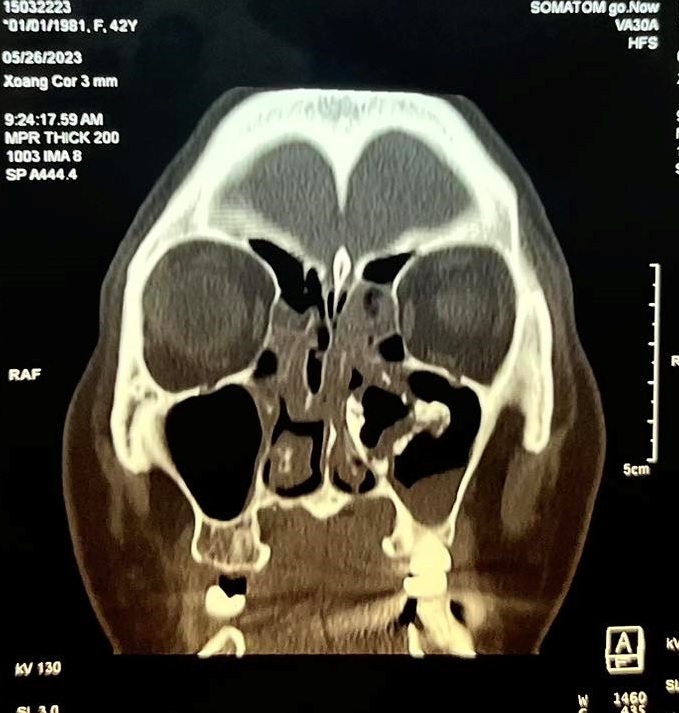

Gần đây bệnh nhân xuất hiện thêm đau nhức vùng mắt trái cùng bên nên đã đến khám tại Bệnh viện Quận 4. Qua nội soi thăm khám và thực hiện chụp CT-Scan phát hiện bệnh nhân có cấu trúc mật độ giống xương dính vào thành trong xoang hàm bên trái, đẩy lệch vách mũi xoang về phía vách ngăn gây hẹp hốc mũi bên trái kèm viêm xoang hàm sàng 2 bên và concha bullosa cuốn mũi giữa bên phải gây tắc nghẽn đường dẫn lưu của xoang hàm bên phải

Hình ảnh CT scans mũi xoang Đánh giá ca lâm sàng, Bác sĩ chuyên khoa II Đào Duy Tường – Trưởng khoa Tai Mũi Họng Bệnh viện Quận 4 nhận định : “ Đây là một trường hợp khá hiếm , tiến triển chậm, bệnh bắt đầu âm thầm ,ít triệu chứng cho đến khi các lỗ thông của xoang bị tắc nghẽn gây ra các triệu chứng đau nhức vùng mặt và khi khối u gây chèn ép hốc mũi bên trái gây cho bệnh nhân có cảm giác nghẹt mũi. Trong trường hợp này phẫu thuật tương đối khó khăn do hốc mũi hẹp, khó tiếp cận khối u , cần phải sử dụng những thiết bị và dụng cụ phẫu thuật chuyên biệt”